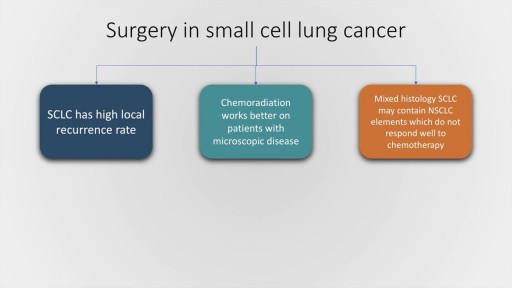

Lung cancer is a type of cancer that begins in the lungs. Your lungs are two spongy organs in your chest that take in oxygen when you inhale and release carbon dioxide when you exhale. Lung cancer is the leading cause of cancer deaths in the United States, among both men and women. Lung cancer claims more lives each year than do colon, prostate, ovarian and breast cancers combined. People who smoke have the greatest risk of lung cancer. The risk of lung cancer increases with the length of time and number of cigarettes you've smoked. If you quit smoking, even after smoking for many years, you can significantly reduce your chances of developing lung cancer.